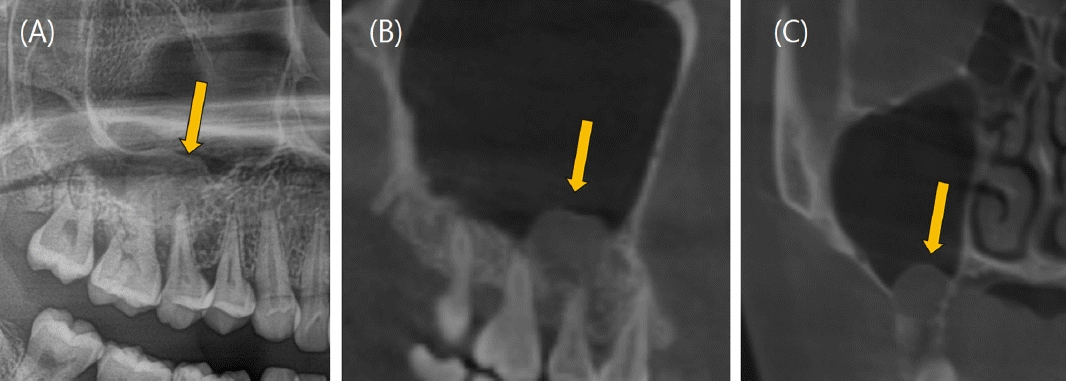

26세 여성이 수개월 전부터 발생한 원인미상의 지속적인 우측 상악 후방부의 잇몸 출혈을 주소로 의뢰되어 구강악안면외과 외래에 내원하였다. 빈혈 이외의 특이 병력은 없었으며, 콘빔 전산화단층촬영(Cone-beam Computed tomography, CBCT)과 파노라마영상을 포함한 단순 진단 영상에서 우측 상악 제2소구치와 제1대구치의 치근단 부위에 직경 12mm의 원형 낭종(Cystic lesion)으로 보이는 병소와 이에 동반된 협측 치조골의 골 침식(Bone erosion)이 관찰되었다(Fig. 1). 병소와 연관되어 있는 치아인 우측 상악 제2소구치와 제1대구치는 전기 치수검사(Electric pulp test)상 생활력이 있었으며, 필요시 술 후에 증상관찰 후 근관 치료를 시행하기로 계획하였다. 방사선 소견 상 반구형의 낭성 종괴, 부드럽고 매끈한 외부경계로 인해 상악동의 점액성 저류낭종(Maxillary mucous retention cyst)일 가능성도 존재했으나 콘빔 전산화단층촬영(CBCT) 상에서 치근부와 연결점이 보인다는 점에서 확률이 낮다고 판단했다[14]. 결국 치근단낭종으로 임시 진단을 내린 후 일주일 뒤 구강악안면외과 외래에서 낭종 적출술을 계획하였다. 빈혈의 기왕력이 있어 일반혈액검사를 실시한 결과, 헤모글로빈 6.7 g/dL, 혈소판 321,000/uL, 프로트롬빈 시간(Prothrombin Time, PT) 13.2 sec, 82.3%, INR 1.11, activated PTT(Partial Thromboplastin Time) 27.9로 외래 수술 시행 전 낮은 헤모글로빈 수치가 관찰되었지만 어지럼증과 같은 임상적 증상은 없었다.구강악안면외과 외래에서 1:100,000 에피네프린이 함유된 2% 리도카인(Lidocaine) 국소마취 하에 낭종 적출술을 시도했으나 수술 중 기구를 치근단 병소 부위로 접근하자마자 대량 출혈(Massive bleeding)이 발생하였으며, 국소적 지혈을 시도하였으나 전혀 지혈이 되지 않았다. 저혈량성 쇼크(Hypovolemic shock) 위험성이 있어 수술을 중단 후 응급실로 이송하였으며, 즉각적으로 적혈구 수혈 및 체액량 보존을 위해 0.9% 생리식염수로 정맥내 수액 공급을 진행하였다. 이어 구내에 발생한 출혈을 조절하기 위해 이어 영상의학과에 의뢰하여 접형구 개동맥(Sphenopalatine artery)과 상악후상치조동맥(Posterior superior alveolar artery)을 대상으로 색전술(Embolization)이 시행되었다(Fig. 2). 응급색전술은 겔폼(Gelfoam), 33% 아교(Glue), 코일(Coil)을 사용하였으며, 성공적으로 출혈을 조절할 수 있었다. 색전술을 시행한 다음날 적절한 혈관 폐색이 이루어졌는지 확인을 위해 전산화 단층 혈관 조영술(Computed tomographic angiography) 촬영을 진행하였다. 접형구개동맥이 폐색되어 있음을 확인하였고, 공급혈관(Feeding vessel) 내에 코일이 적절히 위치해 있었으며, 후상치조동맥에서 기원한 분지 내에서 병변 주변으로 이루어진 glue casting이 관찰되었다(Fig. 3). 이러한 영상 판독 결과를 통해 병변의 혈관 공급이 성공적으로 차단되었음을 확인하였다. 골내 혈관종의 다양한 방사선소견으로 인해 초기에 치근단낭종으로 오인되었음을 확인하였고, 이에 따라 낭종적출술이 아닌 골내혈관종의 수술적 절제를 계획하였다.색전술을 시행한지 이틀 째에 국소마취 하 혈관종의 절제술이 이루어졌다. 협측으로 접근하여 15번 외과용 칼(No.15 Surgical blade)와 골막기자(Periosteal elevator)로 조심스럽게 골막점막피판을 거상한 후에 종양을 주변 조직으로부터 박리하여 모스키토 지혈겸자(Mosquito forcep)로 종양을 제거하였다. 이 과정에서 치근단이 병변과 긴밀하게 연접하고 있는 상악 우측 제2소구치의 경우, 협측 골이 상당히 소실되어 있는 상태로 3도의 동요도를 보여 결국 발치를 하기로 결정하였다. 골 결손 부위와 발치와는 추후 임플란트 식립을 고려해 이종골 이식재와 흡수성 차폐막을 적용해 골이식을 시행하였다.수술적 제거 이후 2개월 추적관찰에서 재발 또는 잔여 증상은 관찰되지 않았다. 임상검사 및 방사선 영상검사에서 골 치유가 만족스럽게 이루어졌으며, 우측 상악 제1대구치에서 동요 또는 타진 통증 없이 환자는 무증상 상태를 유지하였다(Fig. 4). 수술 3개월 후 환자는 안정적인 골 치유와 충분한 각화 치은이 생성된 것을 확인되어 우측 상악 제2소구치부위의 고정체 식립을 위한 임플란트 1차 수술을 시행하였다. 이어 3개월 뒤 임플란트 치유지대주를 연결하는 임플란트 2차 수술 및 상부 보철물 수복을 완료하였으며, 경과 관찰 시 수술부위의 별다른 증상이나 재발의 증거는 없었고, 합병증은 발생하지 않았다.

Figure 3.

Vascular CT(Computed tomographic) angiography performed one day after embolization shows a dome-shaped lesion consistent with a hemangioma. A: coronal view B: sagittal view